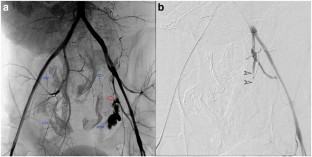

Fig. 2